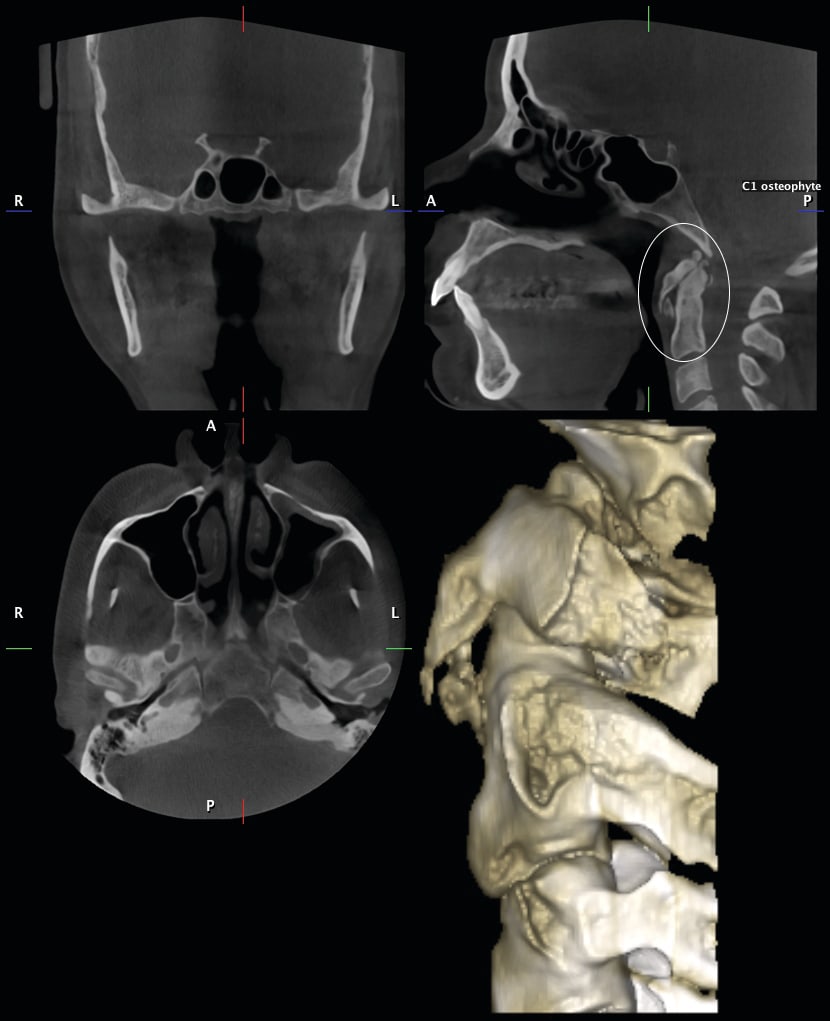

7. Any patient suspected of having an compromised airway. Granted, this is not known until the patient is scanned. However, if there is an inadequate airway, the location of the constriction could determine the type of treatment the patient receives. It could change the treatment plan from a camouflaged treatment to a mandibular advancement for example. A traditional ceph is not adequate in determining the size of an airway. The subject of imaging and treating compromised airway patients is experiencing more advancement in dentistry than any other subject. It is this clinician’s opinion that the orthodontic specialist should be the most qualified clinician to aid in the treatment of these types of patients. These patients deserve a multidisciplinary approach, perhaps more than any other type of patient we see in our practices. DICOM images are vitally important for the proper diagnosis and treatment of these individuals. Figure 28 and Figure 29 illustrate an example of this type of patient that had a chief complaint of overjet. She could be treated with the retraction of the upper anteriors. After further imaging, it was decided that a mandibular advancement would best serve her. Also note the osteophyte on C1 that is constricting the airway. This is not a common occurrence. This osteophyte needs to be removed. So the DICOM images changed our treatment plan. Figure 30 illustrates another patient seeking treatment after surgical relapse. This patient will need to be treated with surgery again. Note the restricted airway at the hypo pharynx. This must be treated prior to the re-treatment of this case. Also note the upper centrals have been torque through the lingual cortical bone. These two problems are not viewed with conventional 2D images.

10. Any patient having pathology that is not imaged on the routine two-dimensional radiographs traditionally taken on the orthodontic patient. Again, we are not aware of these conditions that may exist prior to making a decision of what kind of images we need on a patient presenting for orthodontic treatment. Figure 36 through Figure 42 illustrates just a few of the conditions that were discovered on the 3D images but were not evident on the traditional 2D images. The first patient in Figure 36 shows an axial view where C1 is rotated to the patient’s left. This is also restricting the airway. Figure 37 illustrates a patient that was scheduled for a maxillary osteotomy. The maxillary left sinus is not present. This is reported to be a condition that is present in 1:100,000 people. I believe this condition to be more frequent, having seen it in 3 patients in the last 3 years. Figure 38 illustrates in all three planes of space an enlarged pituitary gland. This patient’s pituitary gland had to be removed. Figure 39 shows a patient with a large traumatic bone cyst. This was not readily evident on the pan because the lesion is so large. This was biopsied and was determined to be a traumatic bone cyst. Figure 40 illustrates a large nasal bone cyst. We have discovered several smaller ones over the past three years that were not evident on a pan. This one however, was evident on the pan. The enlarged pineal gland was not demonstrated on the pan or ceph but is evident on this image in the sagittal plane of space. Figure 41 illustrates a osteophyte on C1 of a 26-year-old female. Figure 42 shows a different view. This patient was referred for a sleep study and was diagnosed with severe sleep apnea. The osteophyte has been removed. We have only illustrated a few of the conditions we have discovered.